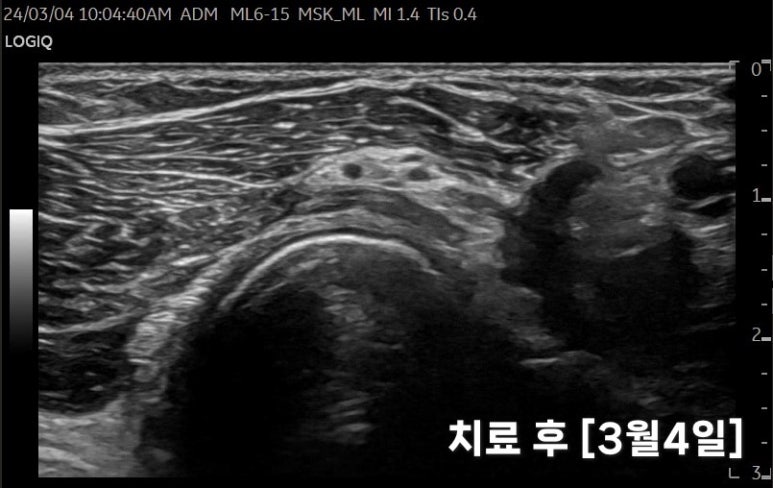

1달간 13회 치료 후

관절 염증을 줄여주는

한약 치료를 하면서

초음파 특수침 치료를

1달간 13회 시술했고요.

증상이 많이 호전되셔서수삼리혈을로체크해봤습니다.

저번 초음파와

차이가 보이시나요?

이처럼

은엑스레이상 잘 보이지 않기에정밀검사를 하는 한의원에서집중 치료가 필요합니다.